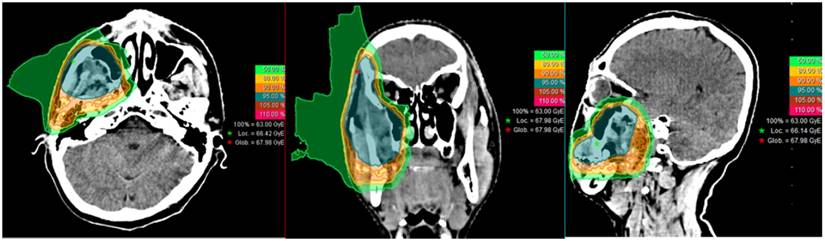

IMCT was delivered with PBS technology. The beam arrangement varied depending on the target volume geometry and dose limits to neighboring organs at risk, such as those with prior radiation exposure. Treatments typically consisted of 2-3 beams with a median of 3 fields. Individual factors such as patient positioning reproducibility and/or beam angles were chosen for optimal dosimetry. For patients with metal dental fillings, beams were delivered from directions that avoided the hardware. Setup accuracy was confirmed with daily orthogonal X-ray using bony landmarks as a reference. Verification CT scans were typically performed on a weekly basis after the second week of the IMCT course to assess any changes in anatomy. A typical treatment plan (a patient with a local recurrence in the buccal region) is shown in Figure 1.

Figure 1

Typical treatment re-irradiation plan of a patient with a locally recurrent soft-tissue sarcoma of the buccal region.